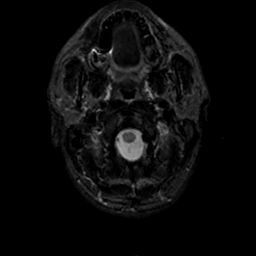

MR Study #19, August 25, 1991 -- Slice #1